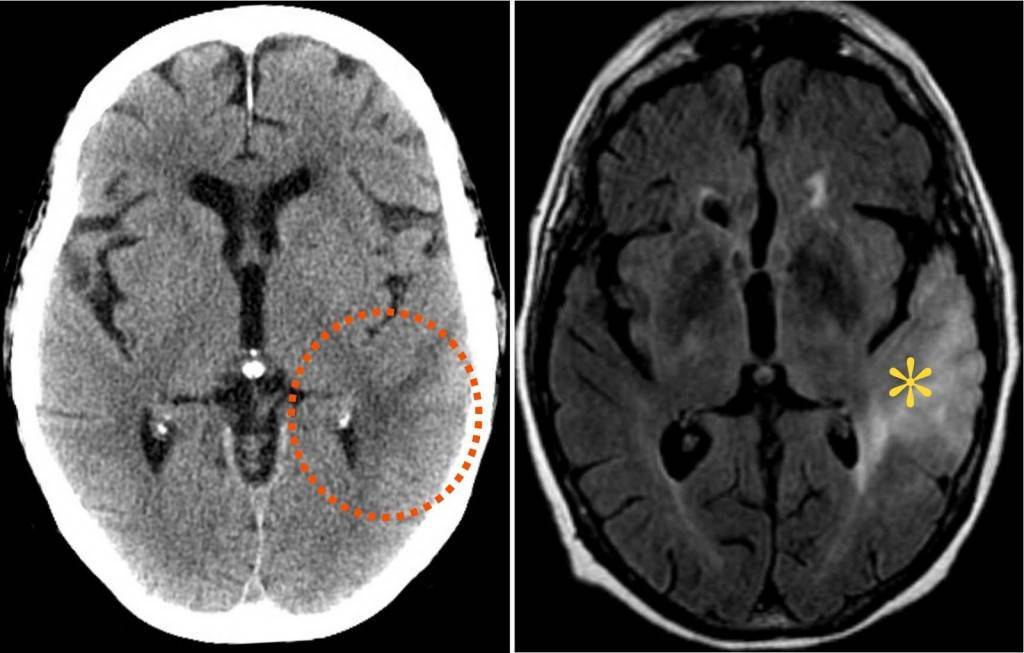

В рамках лечения требующих его опухолей применяются все существующие методы противоопухолевого воздействия: хирургическое удаление, лекарственная терапия, лучевая терапия. Но высокозлокачественные опухоли трудно поддаются излечению ввиду своих особенностей. Их можно сравнить с грибницей, когда то, что врач видит на МРТ и при выполнении операции является лишь уже сформировавшейся макроскопической частью опухоли, а отдельные клетки располагаются в визуально здоровой ткани мозга на большом удалении от основного образования.

Для регулирования состояния пациента проводят постоянный контроль с помощью МРТ. Если опухоль не уменьшается или продолжает расти, выбранный способ терапии не эффективен. Также регулярные исследования проводятся после победой над раком головного мозга, чтобы исключить рецидив патологии.